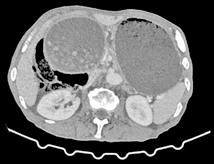

La ecografía abdominal reveló esteatosis hepática sin signos de cirrosis y el ecocardiograma no mostró signos de cardiopatía estructural ni de alto gasto. Por otro lado, ante el descenso de hemoglobina y las quejas del paciente por molestias abdominales, se solicitó una TC toracoabdominal y una colonoscopia para buscar puntos de sangrado o procesos neoplásicos. La colonoscopia no pudo realizarse debido a mala preparación colónica. No obstante, en el TAC toracoabdominal los únicos hallazgos destacables fue ron signos indirectos de hepatopatía crónica con alteración parcheada de la densidad hepática en relación con áreas de esteatosis y engrosamiento de pared del sigma distal que presenta unos contornos mal definidos con alteración de la grasa adyacente en probable relación con proceso inflama torio crónico (como una diverticulitis que se confirmaría posteriormente en una segunda colonoscopia).

Paciente varón de 6 años sin antecedentes de interés, que acudió al Ser vicio de Urgencias 5 horas (h) después de sufrir un trauma contuso en hipogastrio con el manillar de la bicicleta. El paciente presentaba buen estado general y constantes vitales normales pero refería dolor abdominal genera lizado y continuo, sin otros síntomas acompañantes. En la inspección abdo minal se observó una lesión eritematosa-equimótica de aproximadamente 3x3 cm en hipogastrio, levemente dolorosa pero sin alteraciones subyacen tes (Figura 1). El abdomen era blando, depresible y doloroso a la palpación profunda pero sin defensa ni signos de irritación peritoneal. En la analítica sanguínea (AS) se documentó una hemoglobina de 13.5 g/dL, sin elevación de enzimas hepáticas ni pancreáticas, el uroanálisis también fue normal. Se realizó una ecografía de abdomen en la que se visualizaban pequeñas lengüetas de líquido libre intraabdominal y focos de hiperecogenicidad de la grasa mesentérica con engrosamiento focal del peritoneo. Se completó el estudio con una tomografía axial computarizada (TAC) abdominopélvica con contraste que identificó escasa cantidad de líquido libre perihepático e interasas con leve distensión de asas ileales, sin observar otras lesiones. Todo lo anterior sugestivo de contusión mesentérica por lo que se decidió

Las principales herramientas diagnósticas ante la sospecha de perfora ción intestinal son la RxTA, la ecografía y la TAC. El estudio radiológico ha de empezar por la ecografía y posteriormente la TAC, para descartar lesiones más comunes como las hepáticas y esplénicas. Si entonces no se ha visualizado neumoperitoneo y persiste la sospecha de perforación, debe realizarse una RxTA (3). El aire libre se identifica más frecuentemente en la región anterior del abdomen y perihepático, como en nuestro caso. La ecografía además der ser la primera prueba a realizar, es una buena opción en el control evolutivo de lesiones menores. Sus principales ventajas son el bajo costo, amplia disponibilidad y ausencia de radiación, con el inconve niente de la dependencia del observador (8). Respecto a la RxTA, la tasa de visualización de aire libre subdiafragmático en la perforación de víscera hueca es del 18-57%, por ello el complemento con otra serie de imágenes diagnósticas, como la TAC, puede ser necesario (3). Los principales hallaz gos tomográficos que sugieren lesión del TGI son el aire extraluminal, extravasación de contraste, líquido libre intraperitoneal, infiltración en la raíz del mesenterio, entre otros (2).